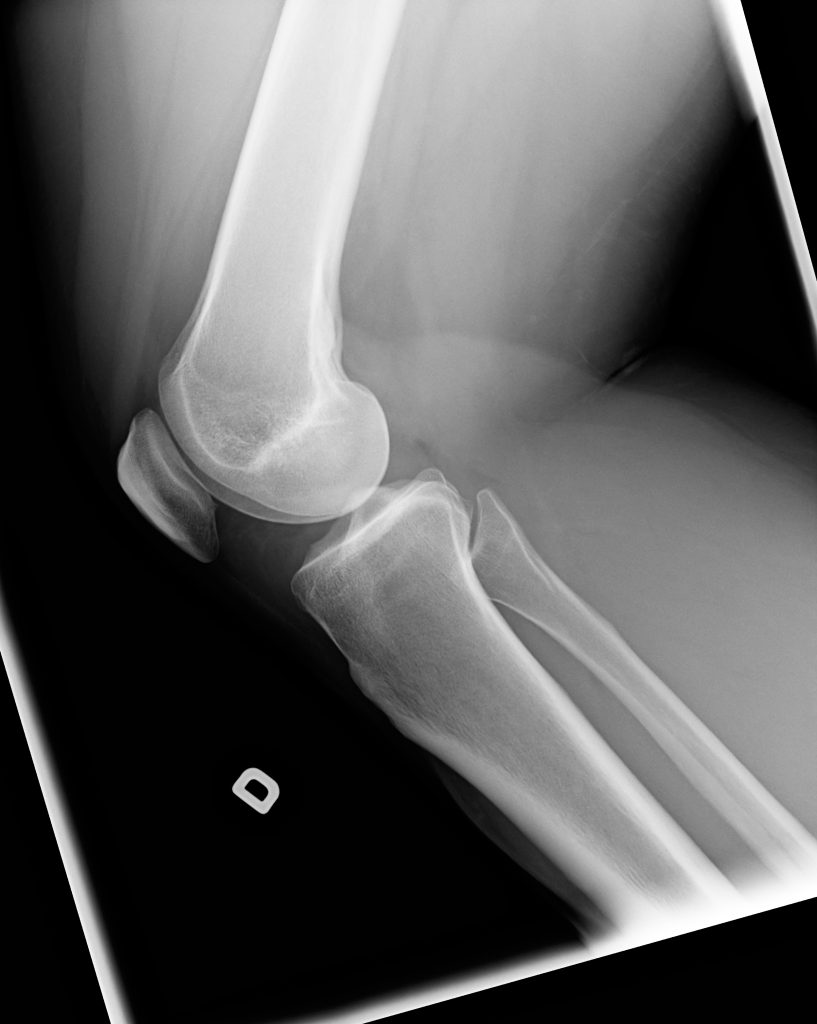

Mithilfe einer Röntgenuntersuchung, die vor allem bei der Erstbegutachtung im Krankenhaus durchgeführt werden sollte, lassen sich knöcherne Begleitverletzungen ausschließen. In weiterer Folge sollte darüber hinaus das genaue Ausmaß der Verletzung mithilfe einer Magnetresonanztomographie abgeklärt werden. Dabei kann das genaue Ausmaß der Verletzung ermittelt werden und lassen sich mögliche Begleitverletzungen, wie Meniskusrisse, Kreuzbandrisse oder Knorpeldefekte diagnostizieren.